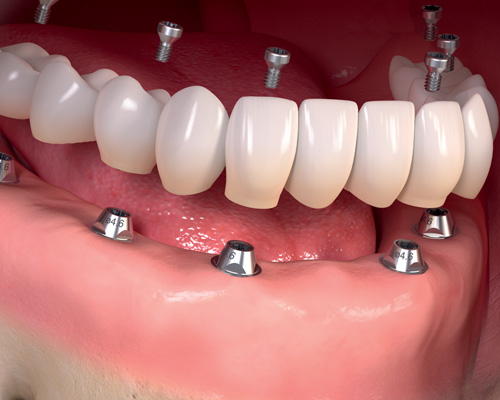

3. Colocación de la prótesis definitiva

El proceso completo para colocar implantes dentales termina con la fijación de la corona o prótesis dental definitiva.

Esta fase se realiza en pasado el tiempo de osteointegración descubrir los implantes que están cubiertos por la encías.

Durante este proceso colocamos los cicatrízales que estarán mínimo 8 días, durante este procedimiento tomamos molde y pendiendo del tipo de prótesis se realizan las pruebas de ajuste adecuadas para asegurar que la conexión con el implante es la adecuada y que el acabado estético esté en armonía con el resto de los dientes del paciente.

Una vez que hemos colocado todos los ajustes podremos colocar la prótesis definitiva sobre los implantes.